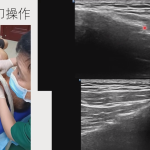

作为一名专注于超声导引下腱鞘炎治疗的疼痛科医生,我每天接诊大量被“弹响指”、“妈妈手”等问题困扰的患者。在临床中,我们最常采用超声导引下针刀联合封闭的治疗方案。这项技术精准、微创,能在可视化条件下松解卡压的腱鞘,消除局部炎症。大多数患者经一次治疗,便能有效解除卡顿和疼痛,一个月左右达到临床痊愈。

在超声实时引导下,针刀精准松解增厚、狭窄的腱鞘(即“管道”壁),扩大其内径,为增粗的肌腱恢复顺畅滑动创造物理空间。这相当于解除了套在肌腱上的“紧箍咒”,直接解除了物理性卡压。 - 封闭(药物注射)的作用:化学性“消炎”与“止痛”